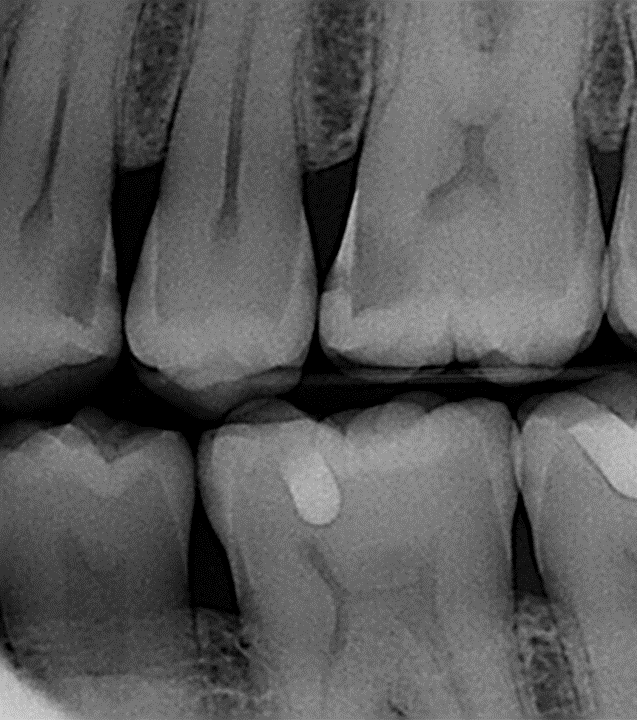

Cosmetic Dentistry – Bioclear

Advanced Anterior Certification Gallery

Basic Anterior Certification Gallery

Basic Posterior Certification Gallery